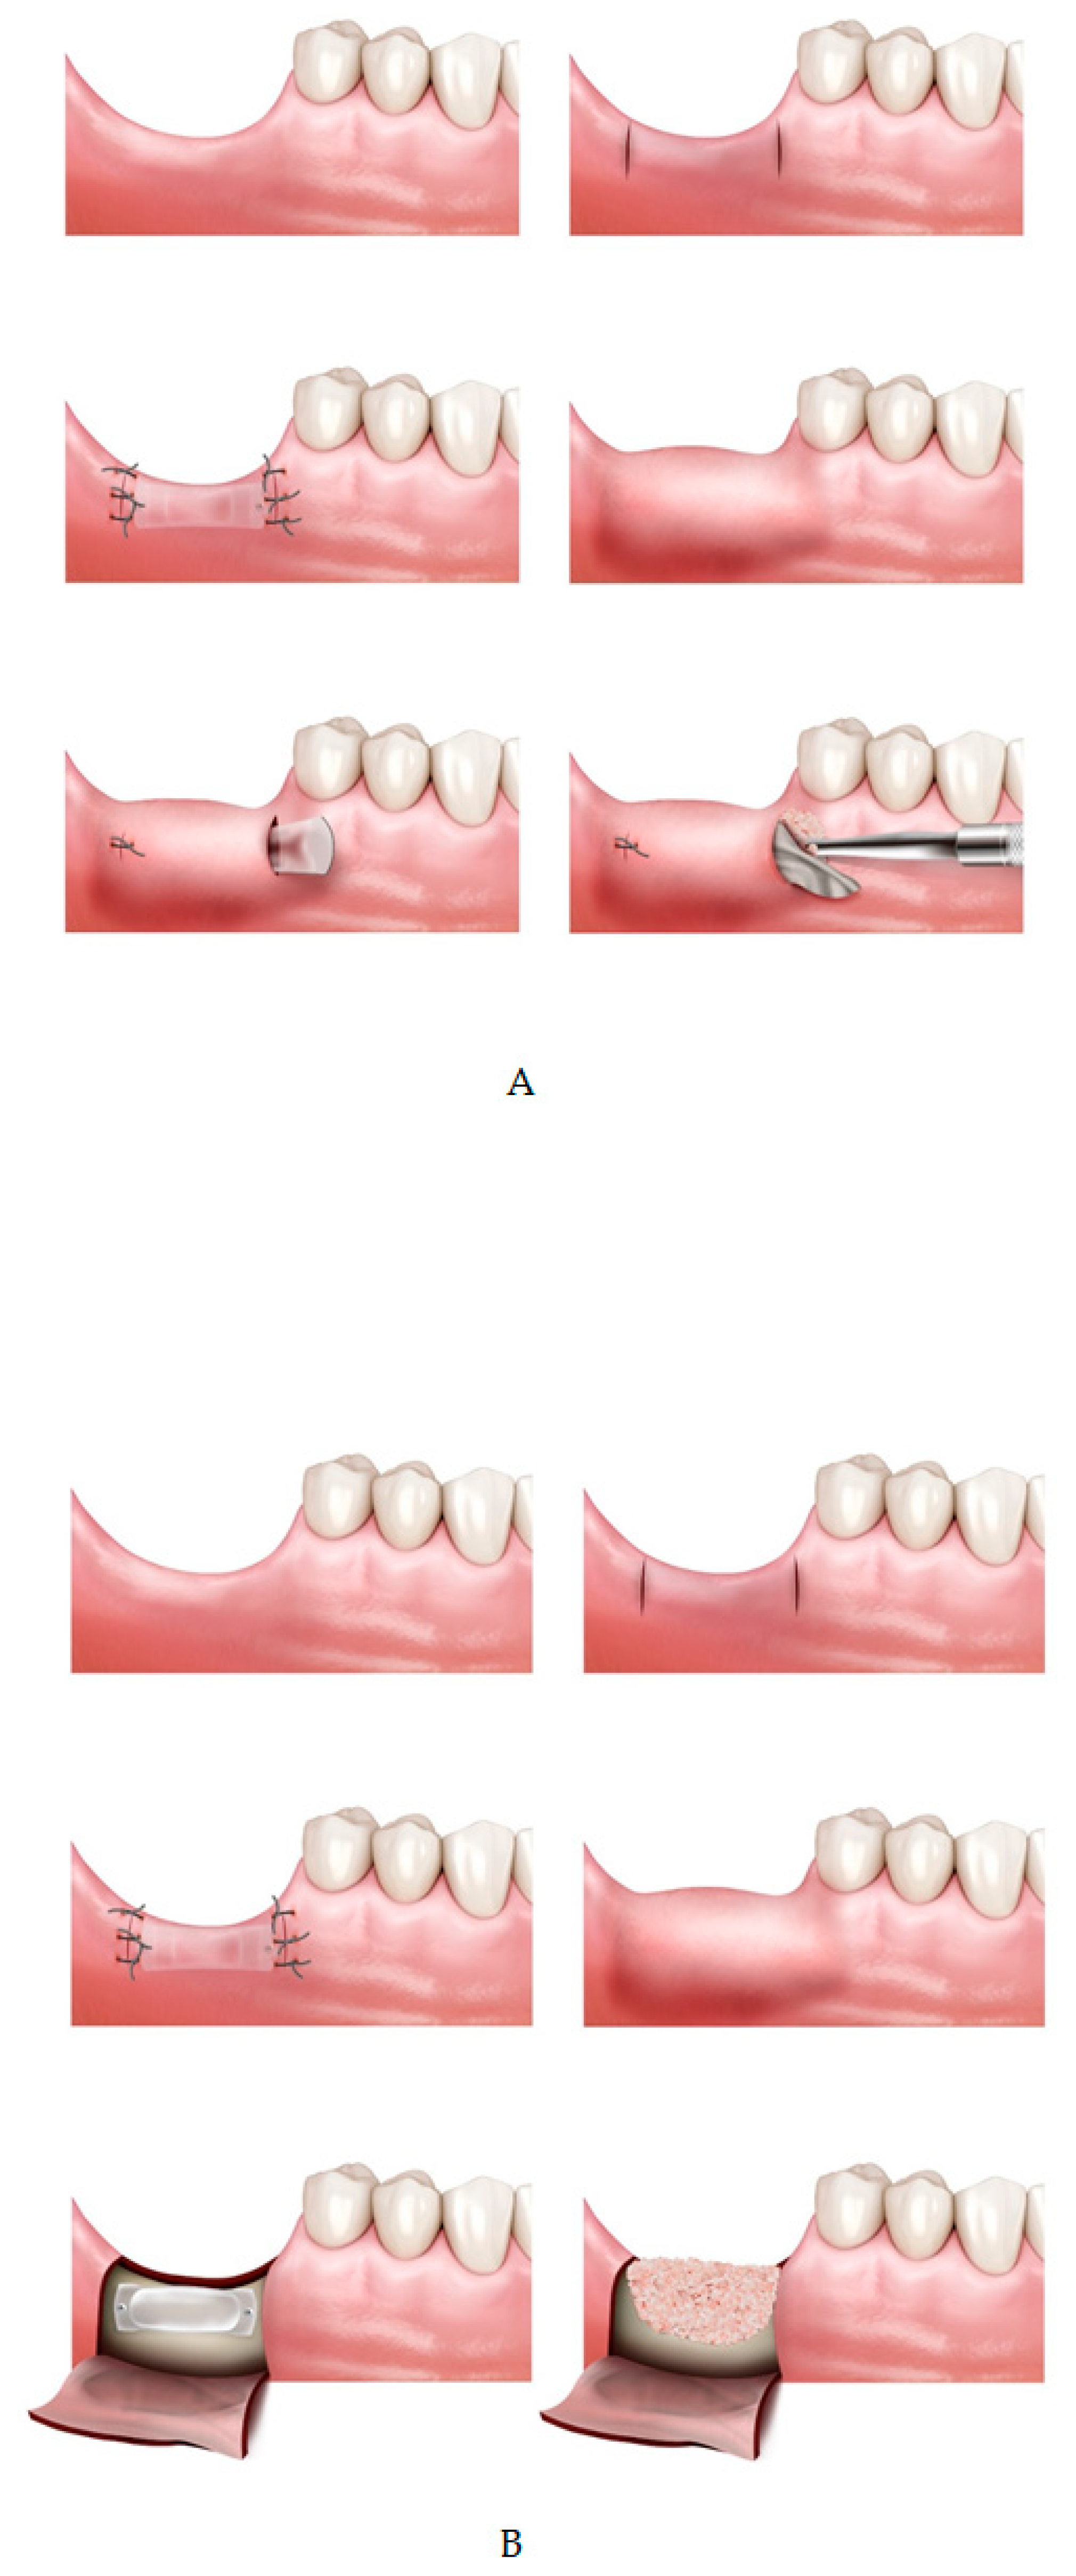

Patients were assigned to one of three study groups: TET (tissue expander–tunneling), TEG (tissue expander–guided bone regeneration; GBR), and control (no expander–GBR) (Figure 2).

All surgical procedures were performed under local anesthesia. In the TET and TEG groups—the tissue expansion group—a vertical incision of 5–10mm from crest to buccal side was made at two—mesial and distal—points with respect to the defective area (visit II). The mucoperiosteum flap was carefully reflected from the bone to form a “tunnel” between the two incisions [20]. A self-inflating soft tissue expander was placed though the created space and fixated with screws to prevent movement or dislocation. The incisions were sutured with 4-0/5-0 Dermalon® monofilament nylon. Suture was removed 14 days post tissue expander insertion (visit III). After 4 weeks post tissue expander insertion, bone augmentation was performed simultaneous to expander removal (visit IV).

In the TET group, incision was made in the same area as that made for expander fixation. After identifying the expander and its fixing screws, they were removed. Subsequently, the collagen membrane tailored to the size of the removed expander (Cytoplast® RTM collagen membrane, Osteogenics, NJ, USA; OssMem®, Osstem, Seoul, Korea) was carefully placed below the periosteum through the space in which the expander was removed and bone was grafted under the membrane using xeno-bone graft material (Bio-Oss®, Geistlich Pharma, Switzerland). Both sides of the incision were sutured and removed 14 days later (visit V).

In the TEG group, unlike TET group in which tunneling graft was performed, bone graft was done in the conventional vertical GBR method. The defect size and type were evaluated, then a d-PTFE titanium-reinforced membrane (Cytoplast® Ti-250XL; Osteogenics, NJ, USA) was trimmed and applied to the defective area. The membrane was placed from the lingual side prior to bone grafting, then was folded over from the lingual to the buccal side after bone graft and fixated using metal pins when necessary. In case of insufficient graft stability, additional tenting screws were applied. After a periosteal releasing incision was made to ensure primary closure of the flap, the area was re-sutured with 4-0/5-0 monofilament nylon and removed 14 days later.

The control group followed the same procedure as the TEG group but without tissue expander insertion. A periosteal releasing incision was made to ensure primary closure of the flap in all cases of the control group. Following bone graft, a d-PTFE titanium-reinforced membrane (Cytoplast® Ti-250XL; Osteogenics, NJ, USA) was placed over the grafted area before flap closure. After each surgical procedure, all patients were instructed of the post-operation guidelines and were prescribed daily chlorhexidine mouthwash (0.2%). Any wound dehiscence, perforations, inflammation, infection, or other postoperative complications were documented at every visit.

Figure 2. (A) Tissue expansion and tunneling graft (TET) group; tissue expander insertion with tunneling bone graft technique. (B) Tissue expansion and conventional bone graft (TEG) group; tissue expander and bone graft with conventional guided bone regeneration technique. (C) Control; full flap guided bone regeneration (GBR) without tissue expander insertion.